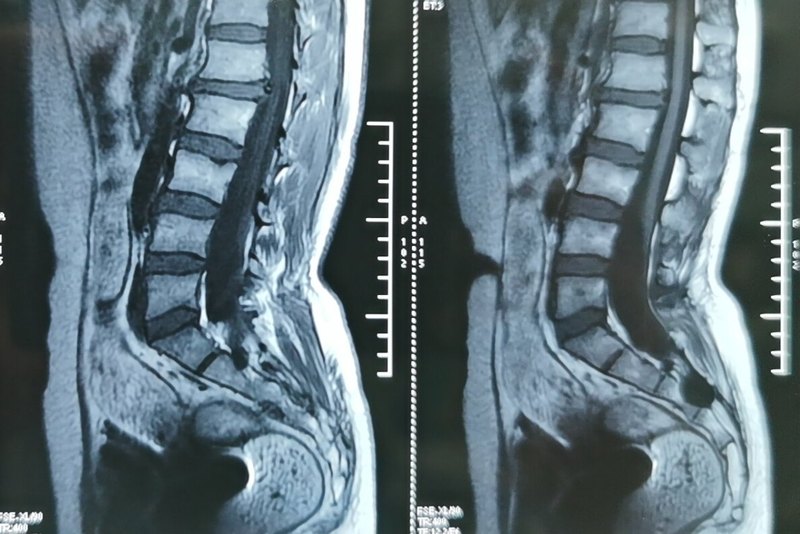

脊髓電刺激治療是目前針對昏迷促醒應用較為廣泛的有創(chuàng)神經調控治療方法之一。其手術本身只是將脊髓電刺激電極及設備植入體內,操作相對簡單。相比而言,術前對于病例的篩選和術后程控對于治療作用的發(fā)揮更為重要。對于患者家屬而言,更為重要的問題是:脊髓電刺激對昏迷促醒究竟有沒有效果?效果有多大?對于這兩個問題,不僅患者家屬,不少臨床醫(yī)生,包括一些專門從事昏迷促醒的醫(yī)生往往也不能確定,有一些專家對此療法持謹慎或消極的觀點。筆者所在團隊是國內從事昏迷促醒專業(yè)最早、規(guī)模最大的團隊之一,完成的脊髓電刺激手術數量全國領先,迄今已完成超過200例昏迷促醒脊髓電刺激手術。筆者本人對于手術全流程治療也有相當的體會和感悟。本著實事求是的精神和態(tài)度,我們拿事實說話,在此特將此前總結的一篇論文分享,該文應是截止目前國內有關此話題的最大病例數的報道,供同道交流,供患者群體參考。脊髓電刺激術治療顱腦創(chuàng)傷后慢性意識障礙的療效分析(附110例報告)夏小雨 楊藝 黨圓圓 陳雪玲 黃瑞景 呂俊 王康 吳杰 林惜玉 何江弘解放軍總醫(yī)院第七醫(yī)學中心神經外科,北京 100700通信作者:何江弘,Email:he_jianghong@sina.cn【摘要】 目的 探討脊髓電刺激術治療顱腦創(chuàng)傷后慢性意識障礙(DOC)患者的療效及其影響因素分析。方法 回顧性分析2011年8月至2017年12月解放軍總醫(yī)院第七醫(yī)學中心神經外科采用脊髓電刺激治療的110例顱腦創(chuàng)傷后慢性DOC患者的臨床資料。術后行頸椎CT掃描以判斷電極植入的位置。術后3、6個月對所有患者行臨床隨訪,隨訪內容包括:神經系統(tǒng)體格檢查、改良昏迷恢復量表(CRS-R)評分。根據患者臨床癥狀轉歸和評分結果共同評價手術療效,分為有效和無效。進一步采用單因素和多因素logistic回歸分析方法探討影響患者療效的危險因素。結果 術后復查頸椎CT,110例患者的電極均植入C2~C4水平的頸部椎管硬膜外。110例患者的刺激參數:頻率5Hz或70Hz,脈寬210us,電壓1-5V,每日開機時間為8~12 h,刺激模式為刺激15 min、間歇15 min。術后6個月,110例患者的療效為,38例有效(其中24例優(yōu)秀,14例改善),72例無效(其中67例無效,5例死亡),總體有效率為34.5%(38/110)。單因素分析結果顯示,年齡、病程、CRS評分以及術前手術推薦標準是影響患者療效的臨床因素(均P<0.05)。進一步多因素logistic回歸分析顯示,術前評估推薦標準是影響患者療效的獨立危險因素(HR=8.179,95% CI:2.171~30.816,P=0.002)。CRS評分是影響患者療效的獨立保護因素(HR=0.304,95% CI:0.095~0.978,P=0.046)。結論 SCS治療DOC療效較好,可作為治療DOC的可行方案之一;術前評估推薦標準是影響DOC患者療效的獨立危險因素?!娟P鍵詞】脊髓電刺激,持續(xù)植物狀態(tài),微意識狀態(tài)基金項目:首都特色基金資助項目(Z171100001017162)Therapeutic effect of spinal cord stimulation on chronic disorders of consciousness after brain injury (Report of 110 cases)Xia Xiaoyu, Yang Yi, Dang Yuanyuan, Chen Xueling, Huang Ruijing, Lv Jun, Wang Kang, Wu Jie, Lin Xiyu, He JianghongCorrespondence: He Jianghong, he_jianghong@sina.cnDepartment of Neurosurgery, the Seventh Medical Center of PLA General Hospital, Beijing 100700, China【Abstract】 Objective To investigate the efficacy and influencing factors of spinal cord stimulation (SCS) in the treatment of patients with chronic disorders of consciousness (DOC) after brain injury. Methods The clinical data of 110 patients with chronic DOC after brain injury were analyzed retrospectively from August 2011 to December 2017 in the Department of Neurosurgery, The Seventh Medical Center of Chinese PLA General Hospital. A CT scan of the cervical spine was performed to show the location of the electrode implantation. All patients underwent clinical follow-up at 3 and 6 months after surgery. The follow-up included: neurological physical examination and modified coma recovery scale (CRS-R) score. According to the patient's clinical symptom outcome and scoring results, the surgical outcome was evaluated and it was divided into effective and ineffective. Univariate and multivariate logistic regression analysis were used to explore risk factors affecting patient outcomes. Results Cervical CT was performed after operation. The electrodes of 110 patients were implanted with cervical spinal epidural C2~C4 level. Stimulation parameters of 110 patients: frequency 5Hz or 70Hz, pulse width 210us, voltage 1-5V, daily start-up time is 8-12 h, stimulation mode is stimulation 15 min, intermittent 15 min. At 6 months after surgery, the efficacy of 110 patients was 38 (effective in 24, 14 improved), 72 were ineffective (67 were ineffective, 5 died), and the overall effective rate was 34.5% (38/110). Univariate analysis showed that age, duration of disease, CRS score, and preoperative surgical recommendations were clinical factors affecting patient outcome (all P < 0.05). Further multivariate logistic regression analysis showed that the preoperative evaluation recommendation was an independent risk factor affecting patient outcome (HR=8.179, 95% CI: 2.171 to 30.816, P=0.002). CRS score was an independent protective factor affecting patient outcome (HR=0.304, 95% CI: 0.095-0.978, P=0.046). Conclusion SCS is effective in the treatment of DOC and can be used as one of the feasible treatments for DOC. The preoperative evaluation recommendation is an independent risk factor for the efficacy of patients with DOC.隨著急救和重癥醫(yī)療技術的發(fā)展,顱腦創(chuàng)傷患者的存活率大大提高,一部分患者從重度昏迷轉歸為慢性意識障礙(disorders of consciousness,DOC)。DOC主要包括植物狀態(tài)(vegetative state, VS)和微意識狀態(tài)(minimally consciousness state, MCS)[1]。傳統(tǒng)治療方法包括藥物、高壓氧、康復理療、感官和環(huán)境刺激等,但療效均欠佳。近年來,諸多研究發(fā)現(xiàn)神經調控治療可能成為治療DOC的有效手段[2-5]。目前,國內多家醫(yī)療機構已開展采用脊髓電刺激治療顱腦創(chuàng)傷后慢性DOC的探索和嘗試[6, 7],而解放軍總醫(yī)院第七醫(yī)學中心神經外科自2011年開展相關工作。本研究回顧性分析2011年8月至2017年12月解放軍總醫(yī)院第七醫(yī)學中心神經外科采用脊髓電刺激治療的110例顱腦創(chuàng)傷后慢性DOC患者的臨床資料,進一步探討其療效和相關的影響因素,以期為臨床醫(yī)生提供參考。 資料與方法1.臨床資料:110例患者中,男72例,女38例;年齡為(41.1±13.8)歲(9~71歲)。病程為(9.6±12.6)個月(3~84個月)。110例患者致昏迷的病因為,顱腦創(chuàng)傷42例(38.2%),缺血缺氧性腦病33例(30.0%),腦出血35例(31.8%,其中腦干出血10例)。對110例患者行改良昏迷恢復量表(coma recovery scale-revised, CRS-R)評分[8],其中77例為植物狀態(tài),33例為微意識狀態(tài)。2.影像學資料:術前采用3.0 T超導型MR儀(美國GE公司)對符合條件的患者(無大面積顱骨缺損、分流泵置入物或無法安靜)行頭顱MRI和靜息態(tài)血氧水依賴性功能MRI(blood oxygenation level-dependent functional MRI,BOLD-fMRI)掃描,以評估患者的腦萎縮程度、關鍵腦區(qū)損害,并計算默認網絡激活保留情況。110例患者中,87例行頭顱MR掃描,均同時行BOLD-fMRI,其中59例患者存在不同程度的腦萎縮情況,32例存在丘腦、腦干軟化病灶。BOLD-fMRI評估顯示,有37例患者默認網絡激活保留較好。3.神經電生理學資料:術前對符合條件的患者(無大面積顱骨缺損或顱骨修補)行腦電圖(electroencephalogram,EEG)[9]、經顱磁刺激聯(lián)合腦電圖(tanscranial magnetic stimulation-electroencephalogram,TMS-EEG)[10]及失匹配負波(mismatch negativity,MMN)檢查[11]。本單位自2015年10月開始開展詳細規(guī)范的神經電生理評估,此前手術的患者神經電生理資料缺如。(1)EEG:術前應用BrainAmp 64 MRplus磁兼容的腦電記錄設備(德國BrainProducts公司)采集患者的EEG,至少記錄20 min。之后由有經驗的臨床醫(yī)生對EEG進行臨床判定,并進一步行功率譜、排序熵等量化腦電圖分析。110例患者中,52名患者接受了腦電檢查,均為異常腦電圖,功率譜分析結果顯示有21名患者額葉頻譜能量以高頻成分(α波)占優(yōu),判讀為較佳。(2)TMS-EEG:對部分患者行使用刺激強度為90%運動閾值的TMS脈沖作用于皮質特定靶點,同時記錄脈沖誘發(fā)腦電?;谡T發(fā)腦電分析多個指標:誘發(fā)電位、全局平均電位、腦誘發(fā)激活指標、誘發(fā)網絡以及誘發(fā)腦電能量分布,并計算干預復雜度(PCI)。110例患者中,有27例完成了TMS-EEG檢查并計算了PCI值,10例PCI值在0.3以上,判讀為較佳。(3)MMN:采用醫(yī)用事件相關電位儀(廣州潤杰公司)進行MMN檢查,記錄4個電極(分別為F3、Fz、Cz、F4)。采用雙耳垂為參考,刺激聲音為純音,標準聲音為800 Hz(90%的出現(xiàn)比例),偏差聲音為1 000 Hz(10%出現(xiàn)比例)。上升時間各為5 ms,聲音強度75 db,刺激間隔1 000 ms。分析數據時,剔除>100 uV的數據段進行疊加平均,計算100~300 ms的MMN幅值。110例患者中,61例患者接收了MMN檢查,其中23例患者MMN波形存在且波幅高于1.5uV,判讀為較佳。3.手術指征:(1)患病時間須超過3個月,且連續(xù)4周以上意識無進行性改善或惡化。(2)臨床評分MCS(即使用CRS-R量表,患者在盯視或視物追蹤及痛覺定位評定中,至少符合其中1項,且重復率>50%);或臨床疑似MCS且神經影像學或神經電生理檢測中至少有1項發(fā)現(xiàn)較明確的證據、證實大腦存在意識活動特征的患者。(3)無嚴重并發(fā)癥及手術禁忌證。根據手術指征的符合情況判斷是否推薦患者手術,符合則推薦手術,預測手術療效較好;否則不推薦手術,預測手術療效欠佳。4.手術方法:對患者行全身麻醉,取側臥位。手術經頸后正中入路,一般以C5棘突為中心,切口取C2~C7,分離肌肉至椎板,咬除 C5部分椎板和黃韌帶,經硬膜外腔將3587A或39286型號的外科刺激電極(美國美敦力公司)植入至 C2~C4水平的頸部椎管硬膜外。2017年2月以前使用3587A電極,共68例,此后使用39286電極,共42例。將脈沖發(fā)生器(美國美敦力公司)放置于前胸壁,通過皮下隧道將電極與脈沖發(fā)生器相連[12]。術后行頸椎CT三維掃描并重建以判斷電極植入的位置。5.術后程控方法:術后1周待患者病情平穩(wěn)后開啟脈沖發(fā)生器。首先根據頸椎CT三維重建圖像選擇開啟的刺激靶點,之后2周在不同的刺激模式和刺激條件對患者進行測試,采用的測試方法包括:臨床評定、腦電圖EEG或功能性近紅外光譜分析(functional near- infrared spectroscopy, fNIRS)。臨床評定為觀察開啟刺激時患者的癥狀表現(xiàn),避免刺激過強誘發(fā)患者肌強直、大汗、呼吸急促、頻繁呻吟等不適表現(xiàn)。參數滴定測試期間每天選定一組刺激參數(包括頻率、脈寬、電壓、電極觸點設定的組合),開啟單一參數連續(xù)刺激30分鐘,分別記錄該組參數刺激前基線20分鐘和刺激后2小時的EEG或fNIRS數據。記錄多組參數刺激前后的數據并分析比較EEG頻譜指標或fNIRS指標的變化,優(yōu)選使腦電頻譜高頻能量增加或腦血氧增加的參數。6.隨訪方法:術后3、6、12個月對所有患者進行臨床隨訪。隨訪方式包括:門診、視頻電話、家訪及其他醫(yī)療機構代評等。隨訪內容包括:神經系統(tǒng)體格檢查、CRS-R評分。根據患者臨床癥狀轉歸和評分結果共同評價手術療效,分為(1)優(yōu)秀:完全清醒或存在穩(wěn)定、持續(xù)的遵囑活動;(2)較好:臨床評定或輔助檢查指標較術前有一定提高,但未達到穩(wěn)定的遵囑活動;(3)無效:較術前無明顯改變或死亡。7.統(tǒng)計學方法:采用SPSS 20.0軟件進行統(tǒng)計學分析。符合正態(tài)分布的計量資料采用均數±標準差(x±s)表示,組間差異采用獨立樣本t檢驗。計數資料采用例數或百分比表示,組間差異采用卡方(X2)檢驗。采用單因素和多因素logistic回歸分析方法評估影響術后療效的獨立危險因素。以P<0.05為差異有統(tǒng)計學意義。結 果1.手術結果:術后復查頸椎CT, 110例患者的電極均植入頸椎的預設靶點(圖1)。110例患者的刺激參數:頻率5Hz或70Hz,脈寬210us,電壓1-5V,每日開機時長為8~12 h,刺激模式為刺激15 min、間歇15 min。術后4例發(fā)生前胸壁皮下血腫或積液,3例發(fā)生切口裂開或切口愈合不良,予以早期抽液、加壓或清創(chuàng)縫合處理后均愈合良好。開機后1例出現(xiàn)頻繁惡心、嘔吐,3例出現(xiàn)癲癇樣抽搐,調整程控參數后癥狀均得到緩解。2.隨訪結果:術后6個月,110例患者的療效為,有效38例(其中24例優(yōu)秀,14例較好),無效72例(其中67例無效,5例死亡)。3.影響術后療效的單因素和多因素logistic回歸分析結果(表1,2):單因素分析結果顯示,年齡、病程、CRS評分以及術前手術推薦標準是影響患者療效的臨床因素(均P<0.05)。進一步多因素logistic回歸分析顯示,術前評估推薦標準是影響患者療效的獨立危險因素(HR=8.179,95% CI:2.171~30.816,P=0.002)。CRS評分是影響患者療效的獨立保護因素(HR=0.304,95% CI:0.095~0.978,P=0.046)。討 論脊髓電刺激SCS治療慢性意識障礙DOC的臨床數據非常有限的。本中心自2011年完成DOC-SCS手術110例,通過隨訪及數據統(tǒng)計學分析,結果顯示,SCS對腦損傷后DOC促醒的總有效率為34.5%。單因素分析結果顯示,年齡、病程、CRS評分以及術前手術推薦標準是影響患者療效的臨床因素(均P<0.05)。進一步多因素logistic回歸分析顯示,術前評估推薦標準是影響患者療效的獨立危險因素而CRS評分是影響患者療效的獨立保護因素。MCS患者的治療效果明顯好于VS患者;各病因組對療效的影響對比無顯著差異;療效隨年齡遞增逐漸下降;療效與性別無關;病程較長并不意味著療效更差。更為有意義的是,結果顯示:評估較好組療效明顯優(yōu)于評估一般組,評估一般組的有效率很低,提示在病人的術前評估及篩選中,臨床及輔助技術的綜合應用,對于提高治療效果具有極為重要的作用。3.1 基于CRS-R評分的意識水平分組間對比結果1988-2013年,有10篇文獻報道了共308例DOC-SCS病例,51.6%有臨床改進[12],本研究總有效率34.5%,略低于此前報道的數據。分析可能原因為:1、本組病例判定治療是否有效的標準嚴格基于CRS-R量表評分,意識狀態(tài)判定具有明確指標及可測量性,而既往研究判斷臨床改進的標準較為寬松。2、本組病例中VS比例高于已有報道,導致有效率下降。本組病例按照基線CRS-R評分區(qū)分為VS和MCS兩組,一般認為,MCS患者意識有關的腦結構損傷更輕,功能磁共振有更多激活腦區(qū)和廣泛連接,因此具有更好的預后[13]。本研究中MCS組有效率69.7%。CRS評分是影響患者療效的獨立保護因素,意味著CRS-R評分更高的MCS患者較VS具有更好的療效和預后,符合預期。3.2 其他療效相關因素分析單因素分析提示:各病因組間對比療效無顯著差異,這與既往研究結論外傷組療效更佳有一定差別[6],盡管從數值上看外傷組有效率最高,但統(tǒng)計學無差異,考慮可能與入組病例數有限有關;隨著年齡遞增,有效率下降。療效與性別無關。一項值得注意的結果是,本研究中單因素分析提示病程較長者療效更佳,多因素分析顯示病程與療效無關。這與我們的傳統(tǒng)印象有一定出入,但與最新的慢性意識障礙處理指南符合[14]。傳統(tǒng)認為病因、病程及年齡是影響預后的重要因素,但根據我們的長期臨床觀察發(fā)現(xiàn),由于個體差異明顯及患病后接受治療的質量與強度均存在較大差別,在同一個時間評定點的意識狀態(tài)也存在巨大差異。因此,病人在接受治療時的意識水平,對預后及治療的反應具有最為重要的影響,病例篩選時應作為首先參考的指標,年齡、病因及病程作為重要影響因素,這提示我們即便對于病程較長的慢性意識障礙患者,仍不應輕易的放棄希望,對于病程尚短的患者,也不必急于立即手術。3.3 病例篩選的輔助診斷技術重要性SCS治療DOC目前并無規(guī)范統(tǒng)一的推薦手術標準。鑒于患病后3個月以內病程具有相當的自然恢復清醒可能,一般建議對于病程>3月的患者方才考慮手術治療,而外傷后DOC患者,具有更長的恢復窗口期,應給與較非外傷患者更長的觀察及治療期。MCS患者相比于VS患者腦功能保留更多,具有更好的預后,因此推薦MCS患者考慮手術促醒治療。但臨床量表評分這種依賴臨床醫(yī)生的行為學評估方法有40%的誤診率[15],很容易錯失有機會促醒的患者。在本組病例中,VS組中有15例患者(近20%)治療有效,若僅僅選擇MCS患者推薦手術,將使這些患者錯失恢復的機會。我們采用的手術推薦標準中結合納入了神經影像學和神經電生理指標。根據手術推薦標準評估,“評估較好”組患者57例,有效34例,對比單純依賴CRS-R評分篩選,納入了更多的可促醒的病例(VS組治療有效的15例患者中11例被納入“評估較好”),“評估一般”而接受手術的53例患者中僅4例有效,且無一例恢復至優(yōu)秀,這既說明該手術推薦標準有較高的臨床實用性,也提示我們今后對于“評估一般”組患者,應對手術格外慎重。3.4手術操作及不良反應脊髓電刺激手術操作在頸椎硬膜外,手術操作過程并不復雜。術后早期(1個月內)可能出現(xiàn)皮下血腫或積液、切口裂開或切口愈合不良的并發(fā)癥,除手術操作因素外,更與患者本身合并的營養(yǎng)不良等因素相關。開機刺激少見嚴重不良反應。但臨床觀察中發(fā)現(xiàn):隨著刺激強度的增加(主要為電壓升高),患者均逐漸出現(xiàn)痛苦表情、肢體屈曲強直等不適表現(xiàn),需要設置合理的刺激強度避免引發(fā)過度不適反應;患者對刺激的耐受程度隨治療時間的延長而提升,但當意識水平明顯提升時,患者對刺激的耐受程度往往迅速降低;完全清醒的患者反饋隨刺激頻率的增加不適感也逐漸增加。3.5 程控經驗目前對于脊髓電刺激的術后程控的經驗仍然十分缺乏。有文獻報道推薦采用 5Hz 低頻電刺激,該頻率刺激可誘發(fā)上肢抽動,而上肢的抽動能誘導病人上肢神經功能的康復[16]。我們在前期研究中測量了脊髓電刺激對微意識狀態(tài)患者腦電的影響[17],并評估了脊髓電刺激對神經生理活動的頻率特異性影響,發(fā)現(xiàn)70hz可能是DOC治療的有效頻率[18, 19]。除刺激頻率外,基于功能性近紅外光譜(fNIRS)技術,還有文獻討論了刺激間隔(ISI)對神經調控作用的影響,發(fā)現(xiàn)較短的ISI可改善前額皮質的血容量[20]。總體而言,目前對程控的理解目前仍較為粗淺,脊髓電刺激促醒治療的潛力尚未充分挖掘,對于神經調控機制的深入研究有望對臨床治療起推動和指導作用。3.6 研究的局限性本研究為回顧性研究,無對照組分析,受研究設計固有缺陷的限制,很難將療效的混雜相關因素排除,特別是難以將治療效應與自發(fā)恢復效應完全的區(qū)分出來。為達此目的理想的實驗設計為平行隨機對照研究,盡管慢性意識障礙患者的臨床情況十分復雜,在這一群體的研究中設置空白對照存在諸多困難[21],較難滿意的實現(xiàn),后續(xù)研究仍應朝這一方向不斷努力,改進實驗設計,進行大樣本的前瞻對照研究,從而增強結果的說服力。4、結論和展望對于慢性意識障礙患者的促醒治療,脊髓電刺激是可行方案之一,特別是對于微意識狀態(tài)患者、外傷病因患者有較理想的治療效果?;谛袨閷W評估的CRS-R量表評分,結合神經影像和神經電生理檢查,可以較好的篩選推薦手術患者。目前的意識判斷和刺激范式設定更多是以臨床觀察為主,未來將逐漸并更多的基于客觀檢測技術評定下的調整?;谀X網絡和DOC意識機制的研究深入,對于程控的探索將會增多,以獲取更佳的療效,或針對不同的意識障礙特征,給與不同的程控參數,從而實現(xiàn)閉環(huán)刺激策略,挖掘提高神經調控治療的療效。參考文獻略。